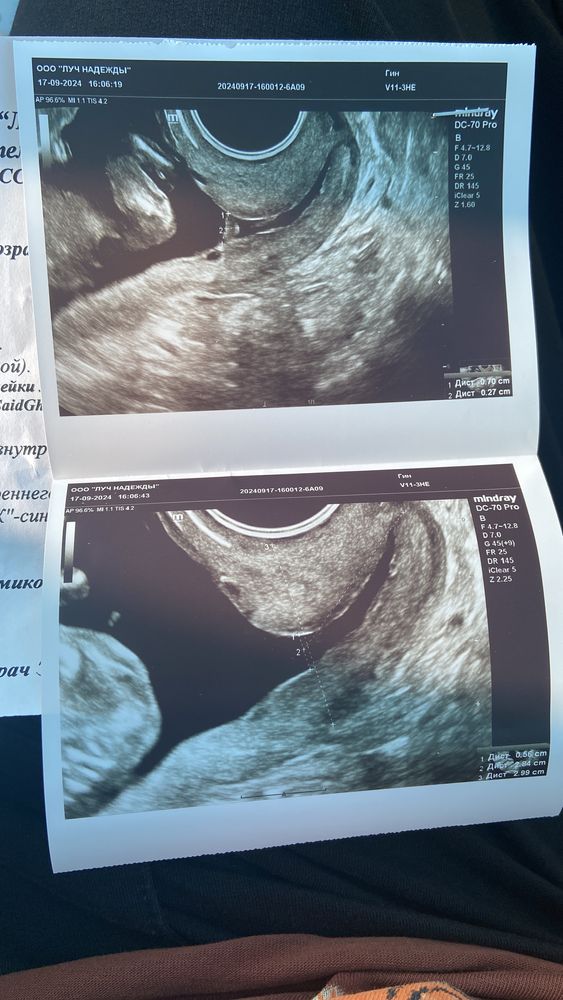

Моя беременность эко ! 4 перенос 18.06.2024. Сегодня 16,1 , все было хорошо скрининг и Нипт сдала! Вчера поехала на Узи шейки и беда, все лучшее сразу [гипер тонус, расширение внутреннего зева и ещё в добавок Сладж.

сейчас лежу в больнице капают меня магнезия и укол дротаверина! Посмотрела на кресле меня доктор сегодня, шейка говорит упругая , но скорее всего писарий поставят ! Капаться 5 дней

Вам если сладж, по идее должны посевы взять и начать антибиотикотерапию, магнезия и дротаверин хорошо что ставят это тонус снимет, а вместо пескари я бы посоветовала швы- обьясню - от пескари риск инфекции намного более вероятный чем от швов, пессарий когда ставят, он признается организмом как инородное тело и становится больше выделений, сильно страдает микрофлора, с пессарием если шейка едет то пессарий не спасёт от открытия, а вот при швах в полном обеззараживании накладывают, потом ничего организму не мешает и даже если шейка поедет дальше то на швах она будет держаться, у меня сейчас 25, с 16 недель швы и пока всё держится только на швах.

Расширение считаться от 10 мм, все, что меньше -норма. Но шейка скорее всего «поползет». Сладж это признак несостоятельности шейки, даже если она нормальная по УЗИ. Лечить надо обязательно и обязательно антибиотиками.

Спасибо Екатерина ! Пока не знаю взяли кровь вчера на инфекцию, мазок вчера и сегодня ! А доктор сказала расширение не критичное так что скорее всего писарий ! Ещё может раскрытие из за тонуса в общем столько много может 🫣 жду ни чего не болит лежу 😅

У меня было похоже, можете в дневнике почитать. Расширения только не было. Точно шить не хотят? У нас по-моему как раз раскрытие было аргументом в пользу шва, у меня его не было, поэтому пессарий. Ещё я в момент обнаружения сладжа настояла на взятии анализа на СРБ. Если бы он был повышен, были бы антибиотики (сладж чаще всего от инфекции - текущей острой или вялотекущей или хронической или недавно прошедшей), сладж давит на шейку, раскрывая ее изнутри.